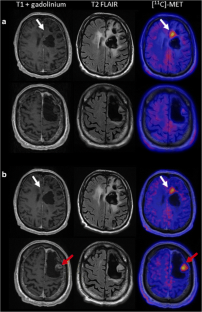

Barker 2nd FG, Chang SM, Huhn SL, Davis RL, Gutin PH, McDermott MW, et al. Age and the risk of anaplasia in magnetic resonance-nonenhancing supratentorial cerebral tumors. Cancer. 1997;80:936–41.

- 55.

Scott JN, Brasher PMA, Sevick RJ, Rewcastle NB, Forsyth PA. How often are nonenhancing supratentorial gliomas malignant? A population study. Neurology. 2002;59:947–9.

- 56.

Kruser TJ, Mehta MP, Robins HI. Pseudoprogression after glioma therapy: a comprehensive review. Expert Rev Neurother. 2013;13:389–403.

- 57.

Duffau H. A new philosophy in surgery for diffuse low-grade glioma (DLGG): oncological and functional outcomes. Neurochirurgie. 2013;59:2–8.

- 58.

Galldiks N, Kracht LW, Dunkl V, Ullrich RT, Vollmar S, Jacobs AH, et al. Imaging of non- or very subtle contrast-enhancing malignant gliomas with [11C]-methionine positron emission tomography. Mol Imaging. 2011;10:453–9.

- 59.

Galldiks N, Ullrich R, Schroeter M, Fink GR, Jacobs AH, Kracht LW. Volumetry of [(11)C]-methionine PET uptake and MRI contrast enhancement in patients with recurrent glioblastoma multiforme. Eur J Nucl Med Mol Imaging. 2010;37:84–92.

- 60.

Bangiyev L, Rossi Espagnet MC, Young R, Shepherd T, Knopp E, Friedman K, et al. Adult brain tumor imaging: state of the art. Semin Roentgenol. 2014;49:39–52.

- 61.

Law M, Yang S, Wang H, Babb JS, Johnson G, Cha S, et al. Glioma grading: sensitivity, specificity, and predictive values of perfusion MR imaging and proton MR spectroscopic imaging compared with conventional MR imaging. AJNR Am J Neuroradiol. 2003;24:1989–98.

- 62.

Law M, Yang S, Babb JS, Knopp EA, Golfinos JG, Zagzag D, et al. Comparison of cerebral blood volume and vascular permeability from dynamic susceptibility contrast-enhanced perfusion MR imaging with glioma grade. AJNR Am J Neuroradiol. 2004;25:746–55.

- 63.

La Fougère C, Suchorska B, Bartenstein P, Kreth F-W, Tonn J-C. Molecular imaging of gliomas with PET: opportunities and limitations. Neuro Oncol. 2011;13:806–19.

- 64.

Ceyssens S, Van Laere K, de Groot T, Goffin J, Bormans G, Mortelmans L. [11C]methionine PET, histopathology, and survival in primary brain tumors and recurrence. AJNR Am J Neuroradiol. 2006;27:1432–7.

- 65.

Ullrich RT, Kracht L, Brunn A, Herholz K, Frommolt P, Miletic H, et al. Methyl-L-11C-methionine PET as a diagnostic marker for malignant progression in patients with glioma. J Nucl Med. 2009;50:1962–8.

- 66.

Singhal T, Narayanan TK, Jacobs MP, Bal C, Mantil JC. 11C-methionine PET for grading and prognostication in gliomas: a comparison study with 18F-FDG PET and contrast enhancement on MRI. J Nucl Med. 2012;53:1709–15.